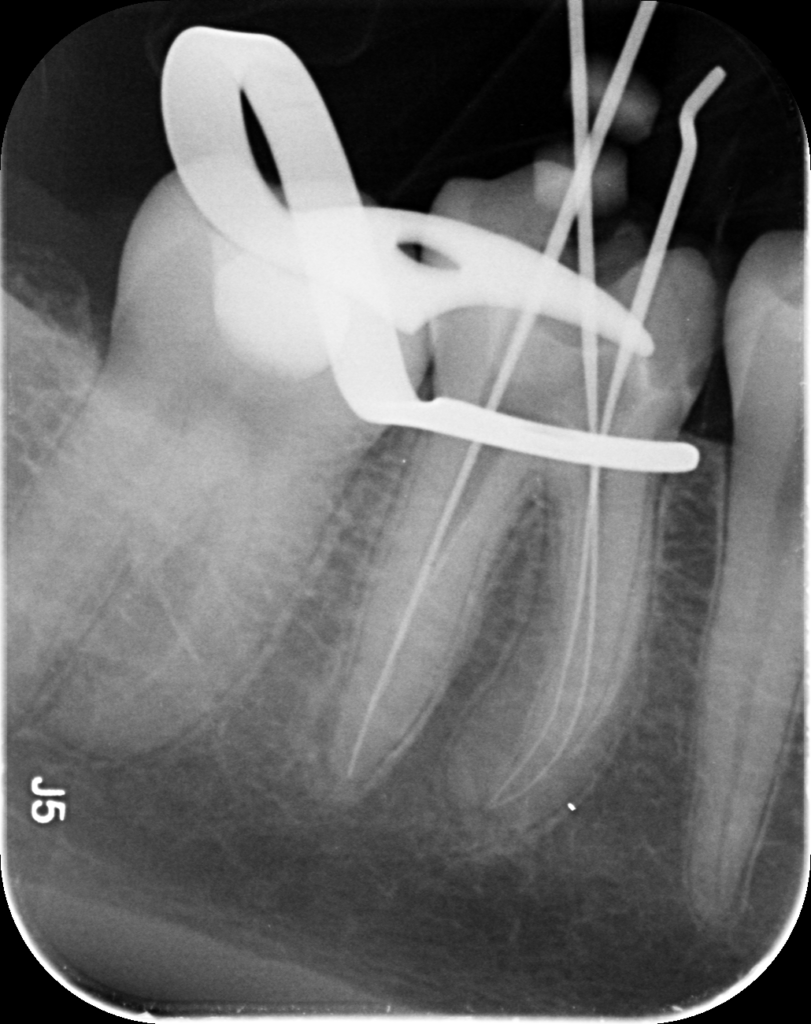

Dantų kanalų gydymas